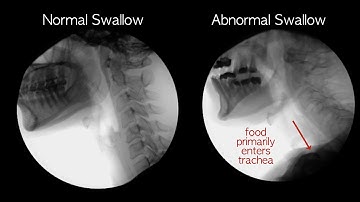

Normal Swallowing and Breathing Animation